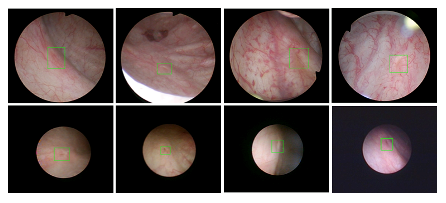

bat365在线平台登录医疗机器人研究院—深睿医疗人工智能医学视频联合实验室成立于2018年7月。PI包括来自于交大生医工学院和电院的三位教授,平台建设目标是将人工智能实时地用到临床医学中去,研究方向包括:1. 建立内窥镜人工智能辅助诊断系统,通过对病灶和解剖结构的实时识别来辅助医生更好地进行微创诊断和治疗;2. 以个性化、定量化的精准诊疗技术为研发目标,重点开展医学影像智能诊断、医学可视化及计算机辅助手术规划、AI及大数据分析在临床诊疗流程中的集成应用等方向的研发。试图利用AI技术、大数据分析技术、3D打印技术、虚拟现实及增强现实技术促进临床的影像诊断、治疗方案设计、预后预测分析等诊疗环节的智能化提升与技术变革;3. 面向运动医学康复、神经退行性疾病量化诊断,以及其他与人体运动相关的疾病诊疗、康复应用,开展视觉三维人体运动的测量、分析与识别研究,通过基于深度学习的视觉检测识别以及相关大数据分析,为相关疾病的诊疗和康复提供AI辅助。具体临床应用包括:关节镜手术术后康复指导和评估、帕金森病的量化诊断、精神疾病的量化诊断与评估、儿童异常行为分析等。

近年来,联合实验室发展了泌尿镜手术实时识别技术,人体姿态精确识别技术,另外围绕小儿先心病手术、肝癌消融手术、数字口腔诊疗的智能化提升等内容进行应用研发。